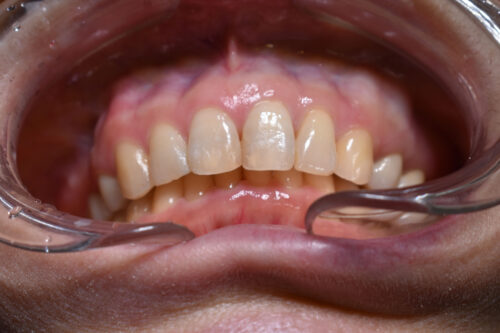

初診時年齢 46歳 女性

歯のでこぼこ(叢生)

左側完全クロスバイトの治療を

左側の小臼歯部から

大臼歯部にかけて

クロスバイトを呈し

過蓋咬合の状態でした。

ワイヤー矯正治療1年2か月後です。